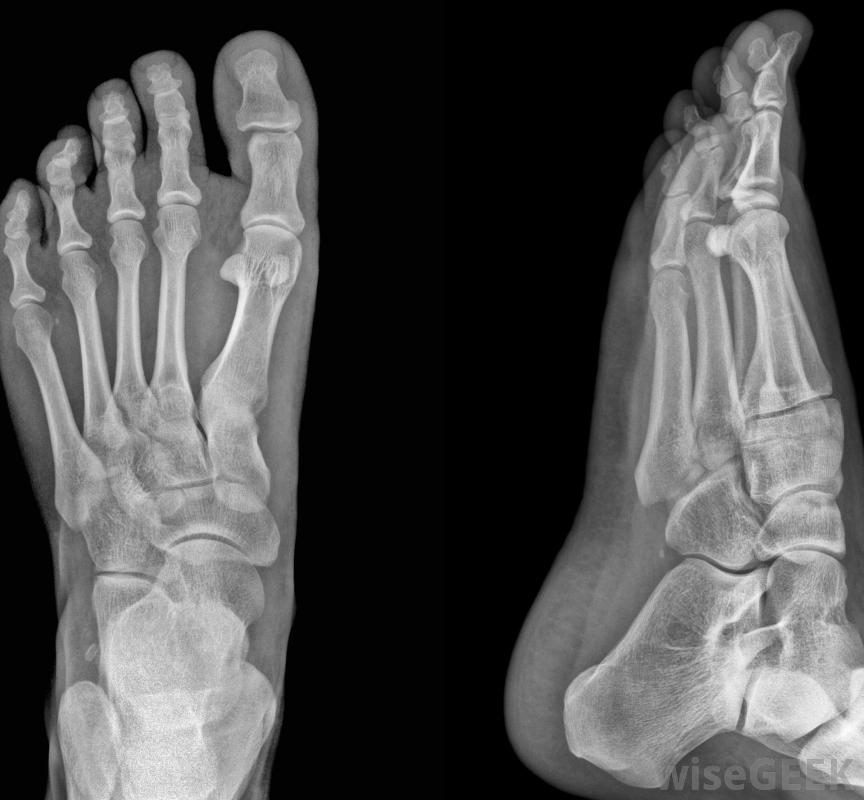

運動機能學研究的是人體內的運動,以及它與一個活的有機體的生理和心理方面的關系,不管這個有機體是人還是動物。運動機能學和物理療法的區別主要在于它在各個研究領域的應用,運動機能學純粹是研究人體及其運動如何在各個層面與人類健康相關的學科,而物理療法則是運動機能學的一門專業,它利用應用程序幫助人類和其他生物促進健康的運動,提高體力和表現物理療法主要依靠鍛煉和身體運動來幫助增強身體。當學生學習一般運動生理學,他或她通常學習對人體疾病和損傷的預防和治療。物理療法的研究也在一定程度上利用了這些信息,然而,運動機能學主要依賴于運用運動和物理運動來幫助增強身體的知識。運動機能學和物理療法在每種實踐中的應用不同。而運動機能學依賴于對身體如何運作的基本理解和知識,物理治療師專門研究一種運動機能學,特別是用手進行身體運動大多數物理治療練習的重點是幫助患者實現全方位的運動。一般運動機能學的某些職業通常使用身體過程和身體健康的知識研究或咨詢的運動。在物理治療中,這些知識也可以使用,然而,更多的工作是對病人進行的,它涉及到通過鍛煉身體來增強體力和靈活性。運動機能學和物理療法的主要區別之一是物理治療師幾乎只為病人工作,運用他們對運動機能學的基本理解,理療師也可以專攻物理治療的某個方面,無論是老年醫學,兒科或肺和心血管物理療法。物理療法是運動機能學的一門專業,研究人體內的運動決定主修運動機能學或物理療法的學生應該知道,有些學校會交替使用這兩個術語。盡管兩個職業選擇在評估和改善健康方面使用了不同的技術,有些學校可能會把物理治療師稱為運動學專業的學生運動機能學和物理療法之間的這種聯系往往是因為物理療法是運動機能學研究的一個分支。大多數健美院校和大學在每門學科中都提供不同的研究內容src="/img/0729/woman-in-physical-therapy-learning-to-walk.jpg"/>一些物理治療師可能專門研究老年醫學。物理治療師經常研究步態,以便發現患者的骨骼問題大多數物理治療師專門為患者工作,并設計康復方案以滿足每個人的需求。